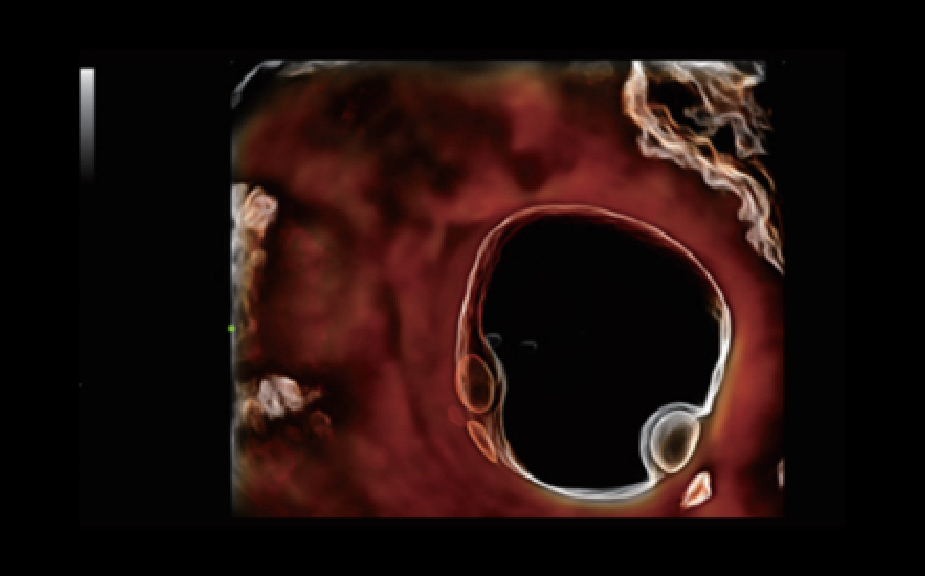

Le Nuewa?I9, con?u spÃĐcialement pour la santÃĐ de la femme et les soins nÃĐonataux, offre une expÃĐrience entiÃĻrement nouvelle gr?ce aux innovations dont il est dotÃĐ, tant à lâintÃĐrieur quâà lâextÃĐrieur. Ces innovations sont dÃĐveloppÃĐes sur la base d'une comprÃĐhension approfondie de scÃĐnarios cliniques complexes, fournissant des rÃĐponses prÃĐcises et adaptÃĐes ainsi qu'une efficacitÃĐ exceptionnelle et une expÃĐrience utilisateur remarquable.

Solution complÃĻte gr?ce au ZST +

La plate-forme ZST+?est une innovation extraordinaire, reprÃĐsentant une ÃĐvolution de lâimagerie ultrasonore. Elle transforme la formation conventionnelle de faisceaux en un traitement basÃĐ sur les canaux de donnÃĐes. Elle repousse les limites de lâimagerie conventionnelle et du compromis entre rÃĐsolution spatiale, rÃĐsolution temporelle et uniformitÃĐ tissulaire en offrant une qualitÃĐ dâimage exceptionnelle pour des solutions dâimagerie infinies et en constante ÃĐvolution.